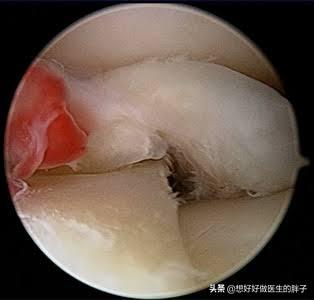

半月板是位于我们关节内非常重要的一种缓冲结构,它是一种软骨结构,在我们的膝关节内,有两块分别为内侧半月板和外侧半月板,而在半月板的两侧是股骨远端以及胫骨近端的关节软骨,半月板以及软骨共同构成了我们膝关节的缓冲系统,这样我们的关节才可以润滑的做关节的屈伸运动或弹跳等这些沉重的运动。

但是由于体重过度使用以及外伤等原因会导致半月板发生退变或者是破裂。这样患者就会表现出明显的行走时疼痛,有一些患者会出现关节的肿胀,而且会出现不能正常蹲起等症状。

如果核磁显示半月板整体的形态还算良好,那么我们完全可以采取休息以及康复锻炼等办法帮助患者缓解症状,而如果半月板整体的形态有了明显的改变,那么说明半月板发生了三度撕裂,这种情况一般要进行关节镜手术治疗,才能帮助患者解决问题。